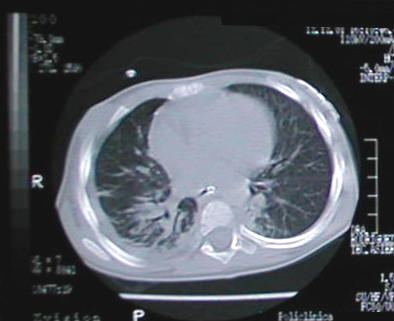

Corte Tomográfico " 1 "

Corte nivel sub carinal de traquea:

Parenquima pulmonar lado derecho en fase neumonica resolutiva, engrosamiento pleural y liquido pleural escaso, del lado izquierdo note el parenquima con areas neumonicas dispersas.